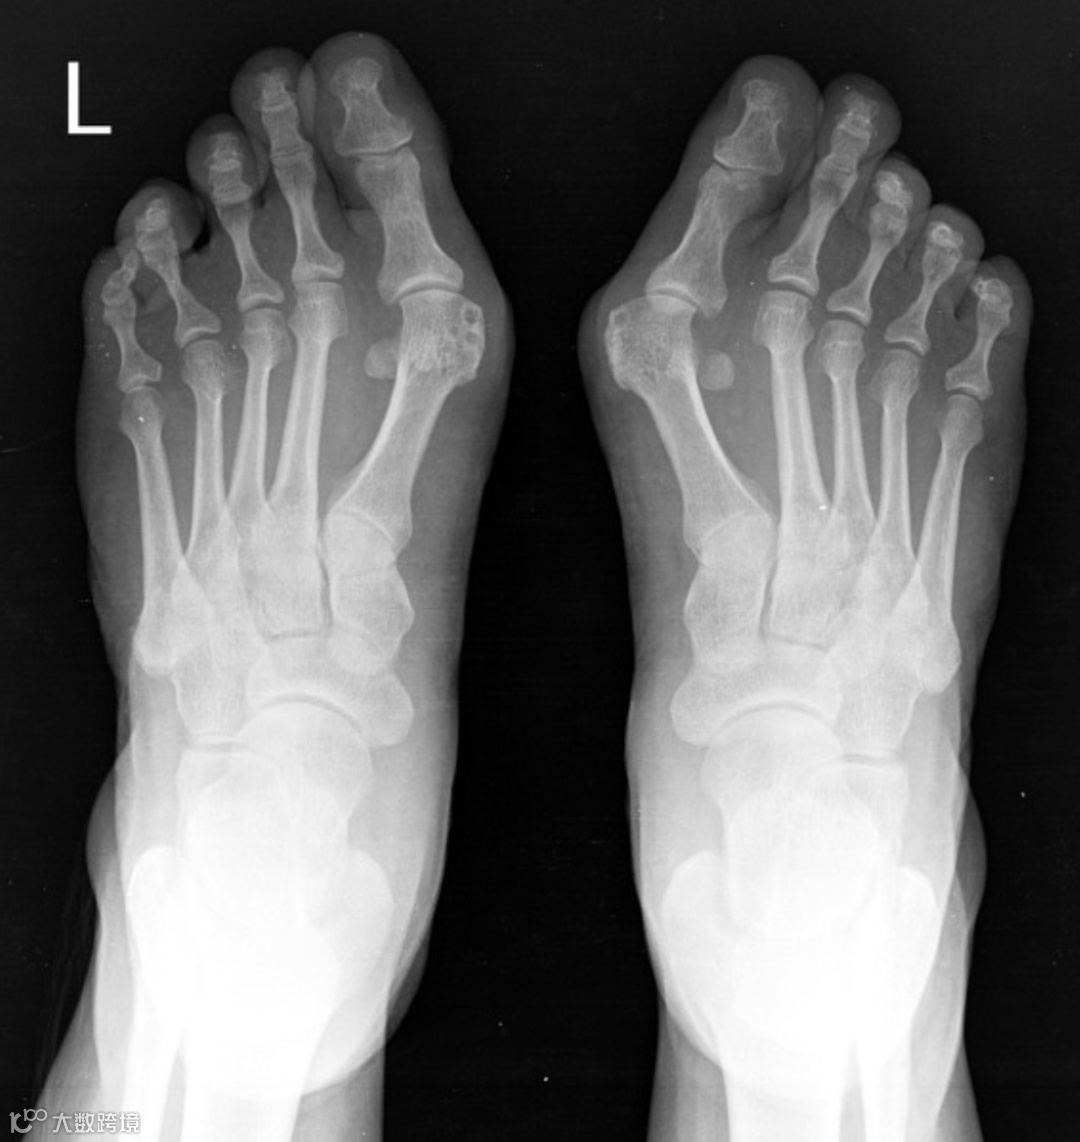

女,45 岁,左足重度拇外翻,第一跖趾角为 45°,跖骨间角为 18°。